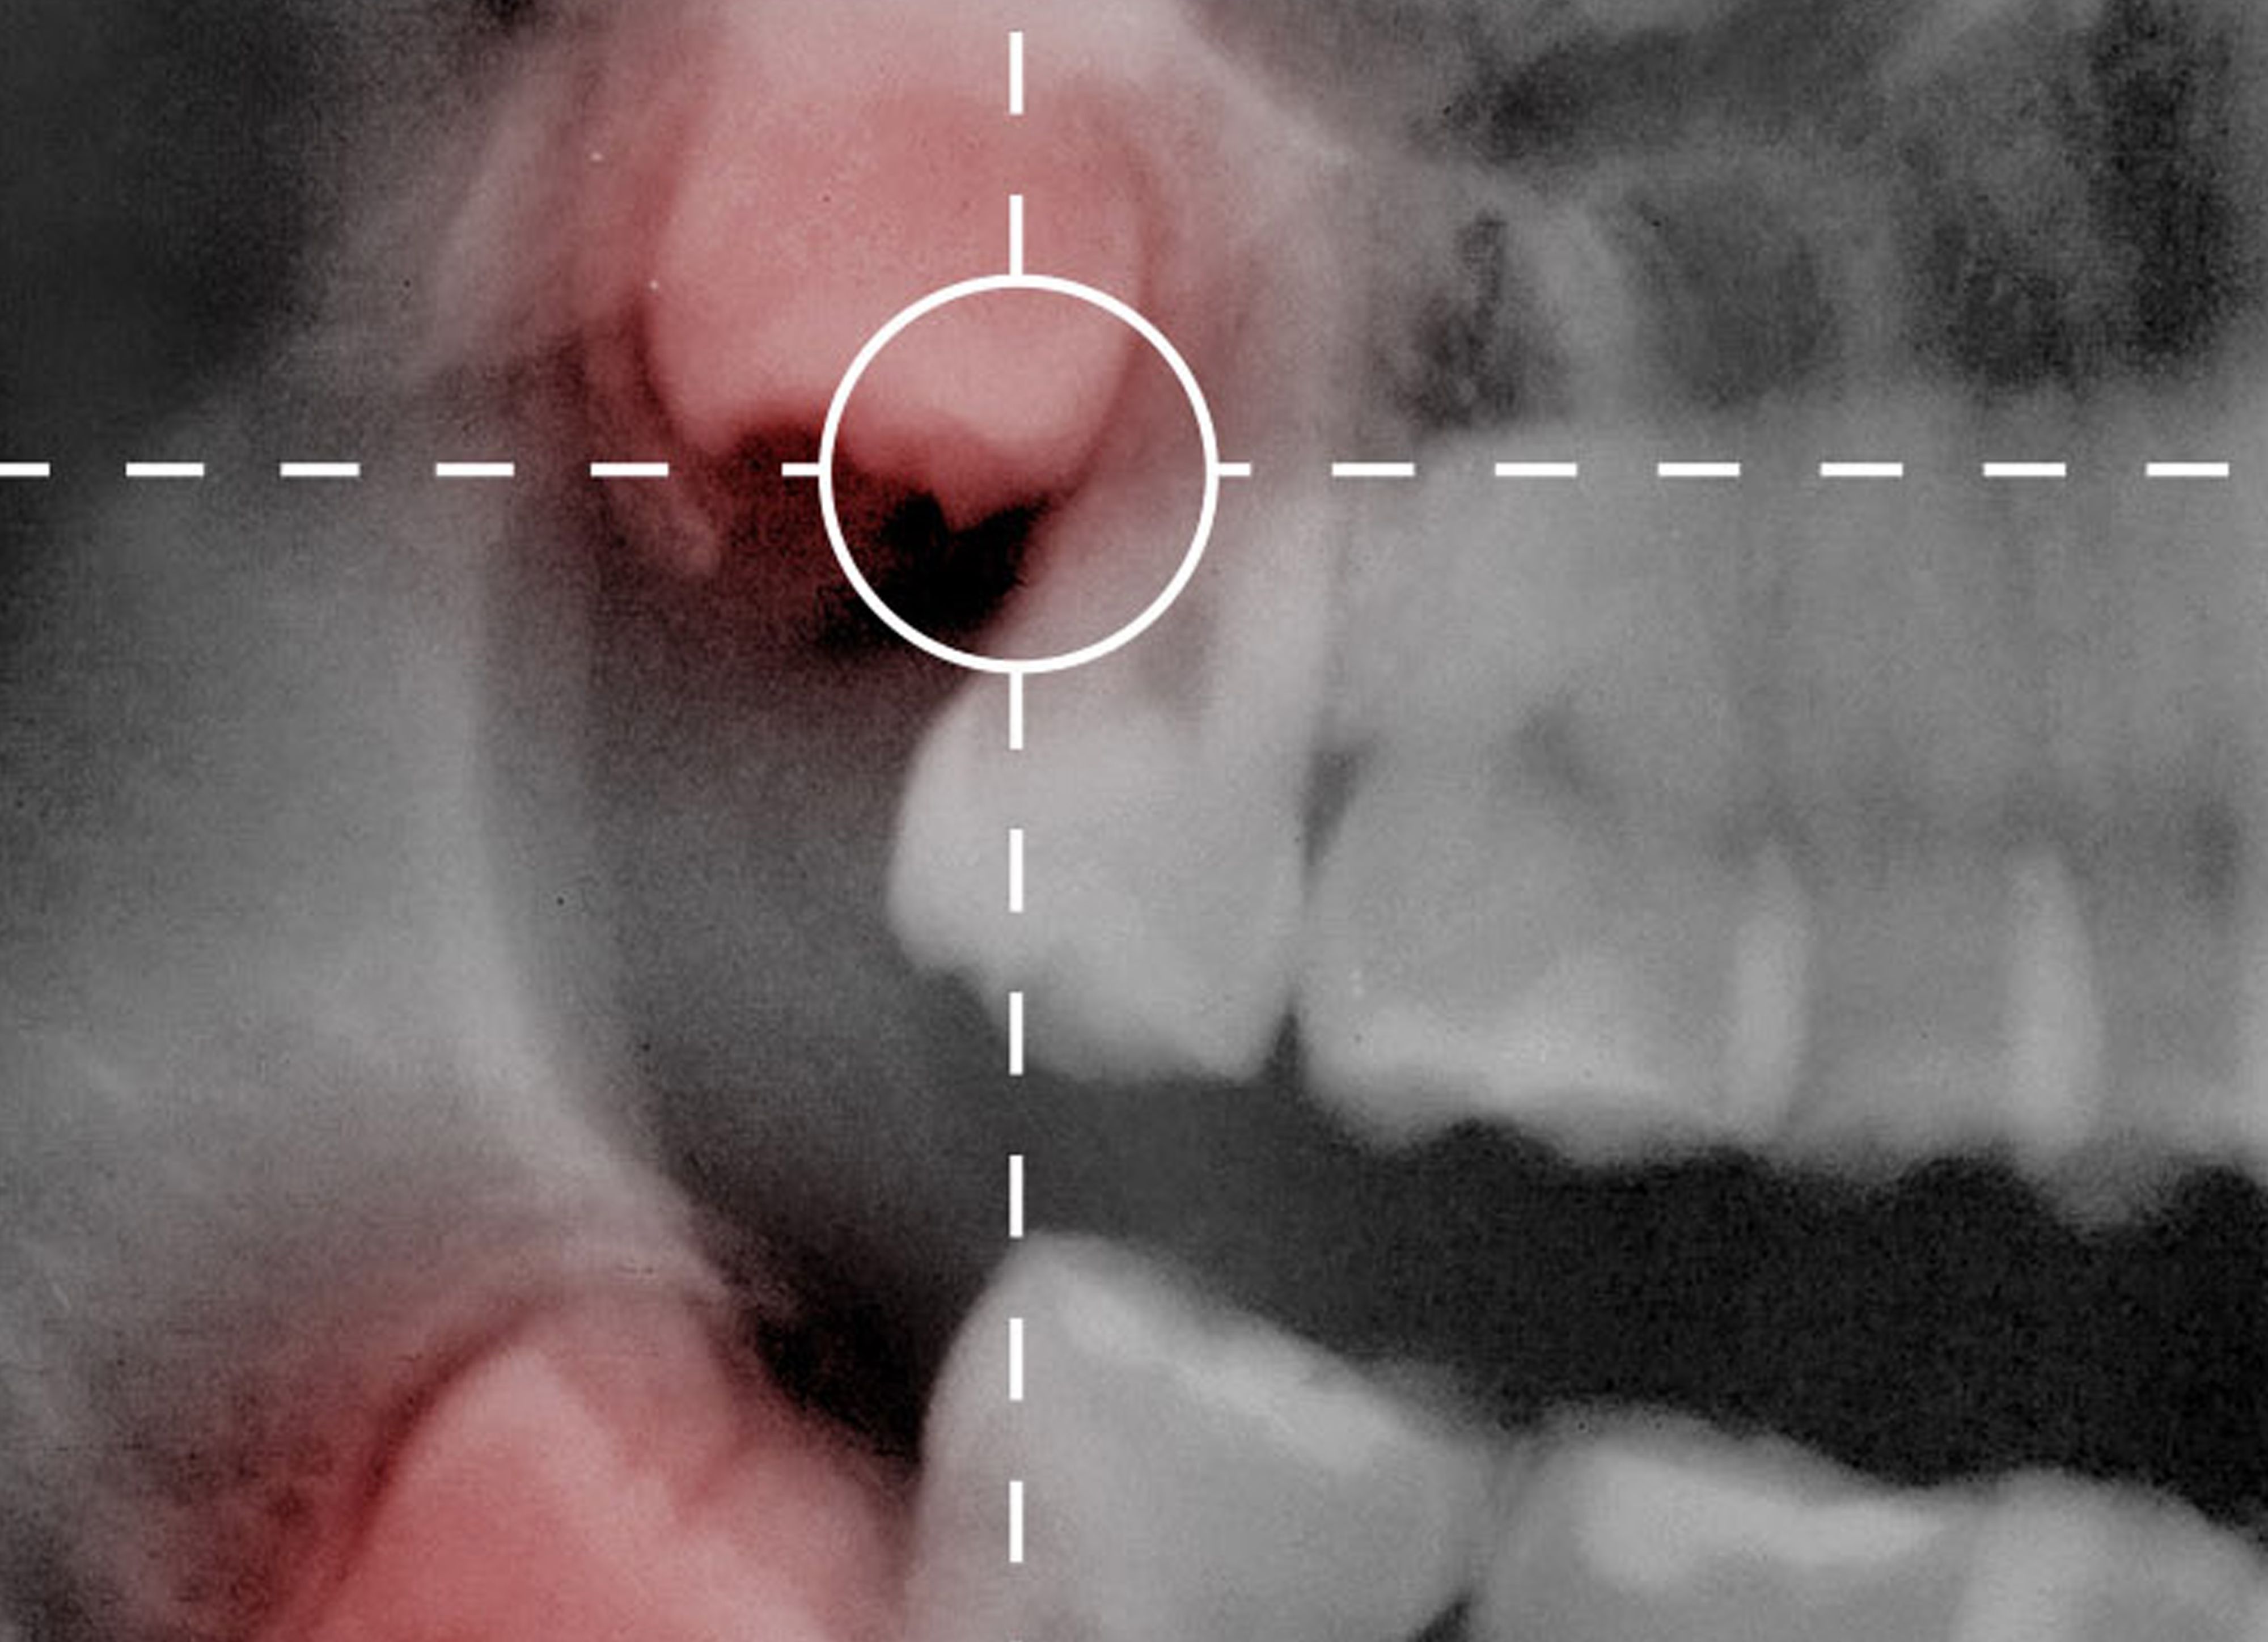

La endodoncia es la rama de la Odontología que trata la patología dental de origen cariogénico, traumatismo o prótesis. El objetivo de esta práctica es la eliminación del paquete vásculo-nervioso del diente con la finalidad de preservar la pieza.